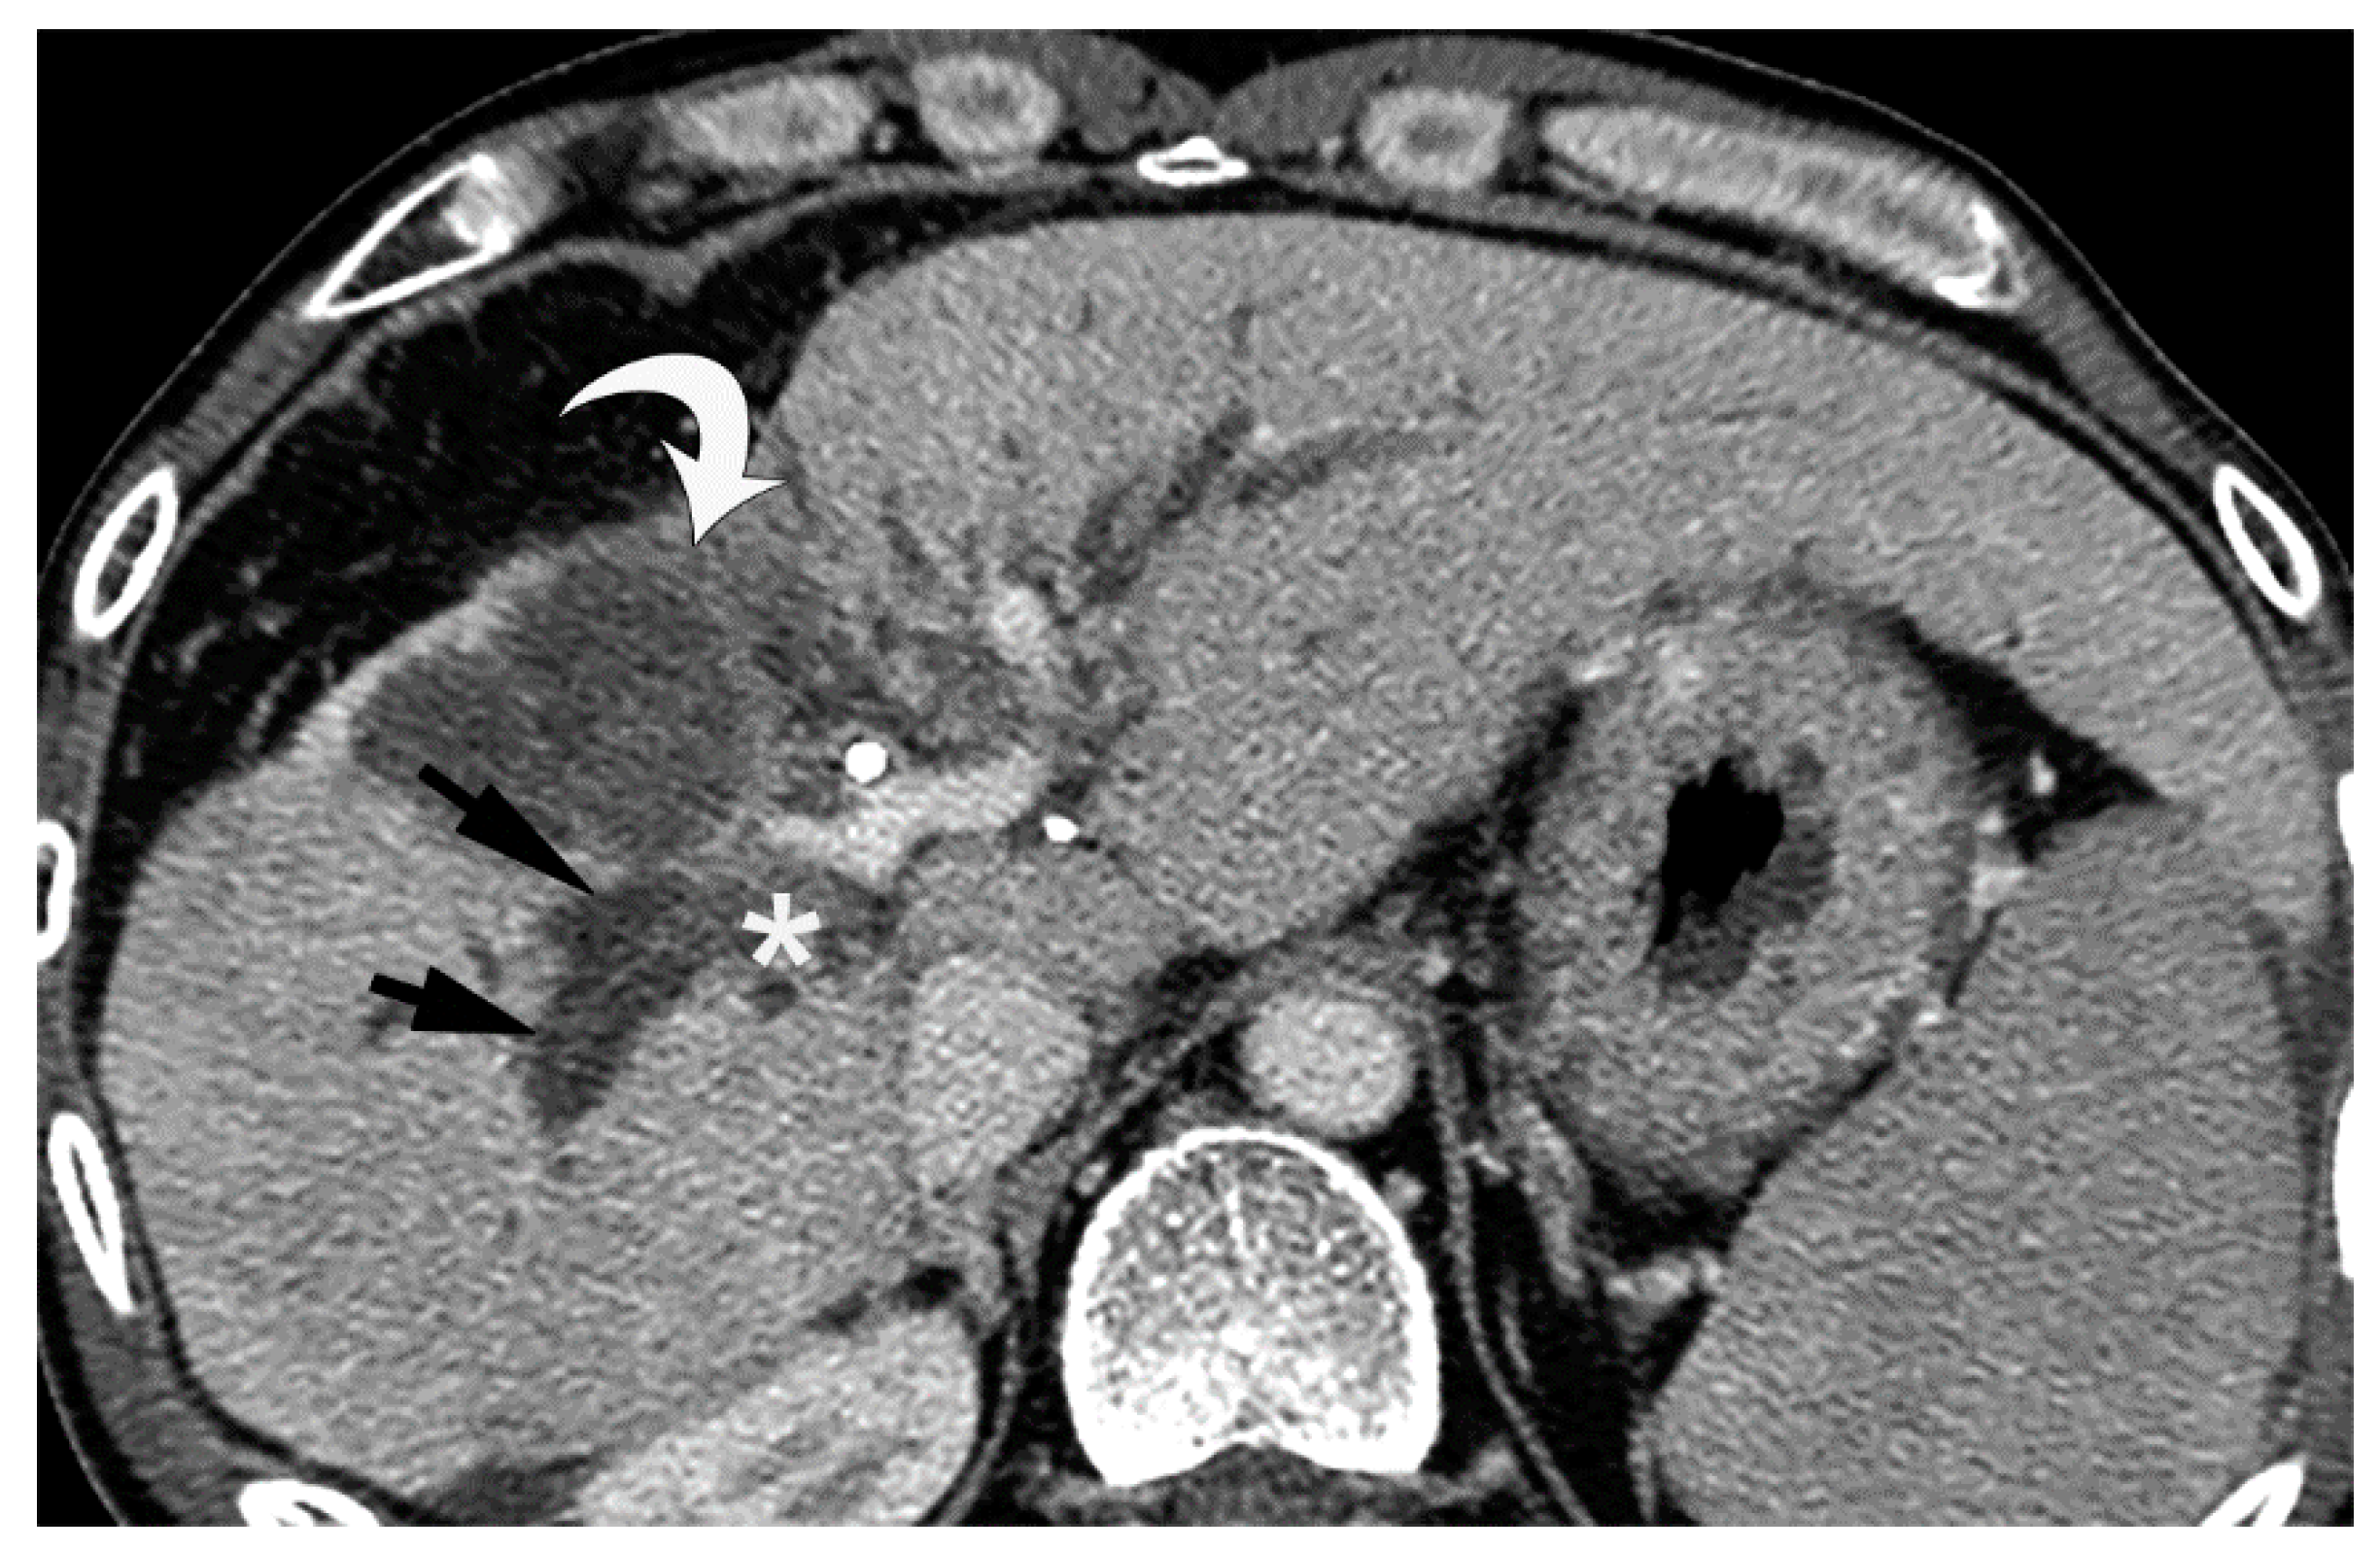

Figure 10. Equilibrium phase image of a contrast-enhanced CT of BDN. A hypodense tubular structure (arrows) is observed in the hepatic hilum of the right lobe. Enhancement of the right main portal branch is discontinued (*), which represents thrombotic obstruction of the portal vein caused by BDN. (Curved arrow is the biloma.).

Since BDN represents a precursor lesion to biloma, intrahepatic biloma formation sometimes coexists with BDN. In such cases, the abovementioned linear hypodense structure, along with the portal tract, connects with the biloma. Advanced BDN can lead to portal vein thrombosis (Figure 10), and may cause segmental staining associated with portal vein perfusion disorders on the arterial phase of contrast-enhanced CT images. After repeated HAIC, BDN cases may show a thickening of the arterial wall and elevated fat density around the artery with catheter insertion, such as the common hepatic artery or proper hepatic artery, which is a finding of hepatic arterial damage caused by HAIC (Figure 11) [29].